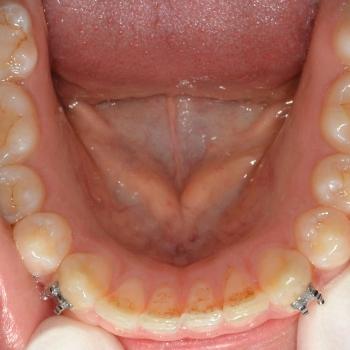

A kezeléshez János hagyományos fém fogszabályozót választott, melyet kiegészítettünk a legkülönfélébb intermaxilláris gumihúzásokkal, illetve egy speciális belső oldali fogszabályozó ívvel, ami segített az alsó őrlőfogakat a nyelv irányába dönteni.

János kitartásának hála a kezelés végén tökéletes esztétikai és funkciós eredményt értünk el.

A kezelés teljes időtartama: 1év 9 hónap